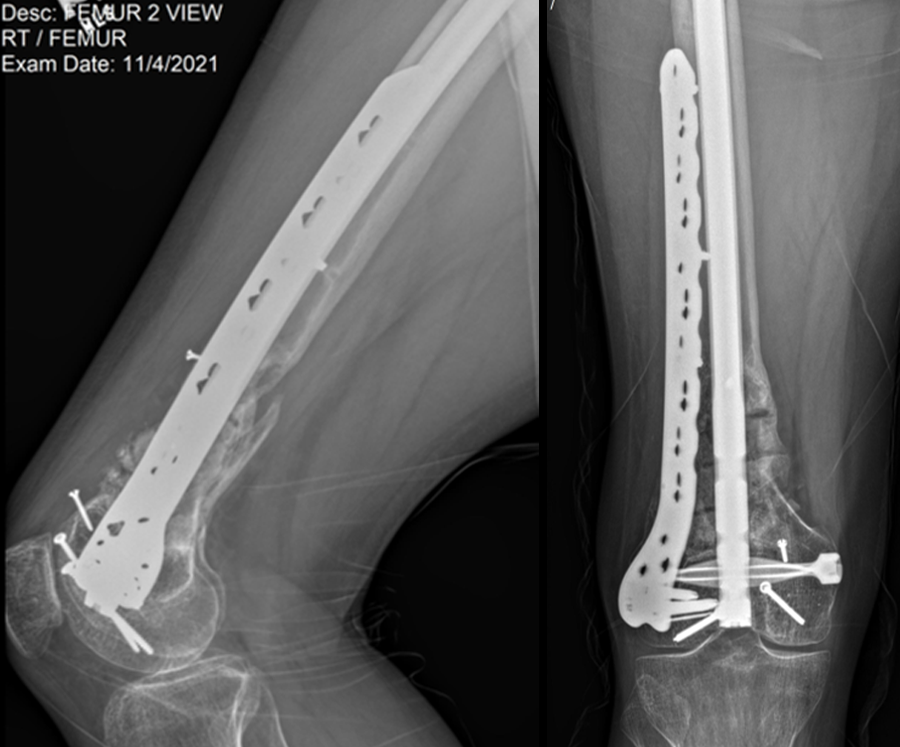

Following the advent of Covid-19 in early 2020, the patient was lost to follow-up for almost one year and was eventually seen again in December 2020 (Fig 8). At this follow-up, a CT scan was planned for the right distal femur and a graft cage ordered. Surgery was scheduled for early 2021.

At the 3-week follow-up (post-graft cage, Fig 12), the patient’s wounds were healthy. He had a range of motion (ROM) of 0–80 in his right knee. He was allowed weight bearing as tolerated (WBAT) with crutches.

At the 3-month follow-up (Fig 13), the patient had a ROM of 0–120 in his right knee. His quadricep muscles had significantly recovered and he was able to WBAT with support from a cane.

At the 6-month follow-up (Fig 14), the patient was able to WBAT on the right lower extremity. He had some ankle pain and a ROM of 0–125 in his right knee. The patient was able to walk without any assistance device.

At the 9-month follow-up (Fig 15), the patient reported nominal knee pain, but more pain in his ankles. The patient had returned to work. He was not undertaking any heavy lifting but was driving the truck and supervising the team. Overall, the patient was happy with the current outcome of surgery.